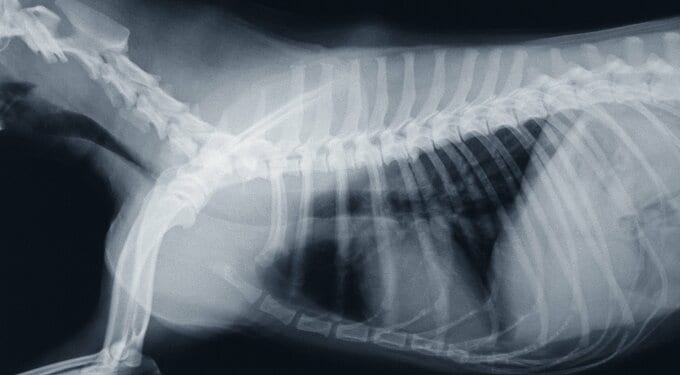

抜歯後のレントゲンを見せてもらうと、犬歯がしっかり根本から抜けていた。犬歯は歯茎に埋まっている根っこがとても長いため、ほかの歯に比べても難しいらしい。

心配していた麻酔も、す〜っと目を覚まして落ち着いていたらしい。全身のレントゲンも見せてもらった。 愛犬のレントゲンを見るのは初めてだ。このあとレントゲン写真を貼るので見たくない方は飛ばしてください。怖いものではないが苦手な方もいますよね。

レントゲン写真を見ながら、骨の状態や気管の説明を受けた。気をつける部分はあるが健康体だと褒めてもらえた。犬の健康に花丸をもらえてうれしい。舌もすごくきれいらしい。